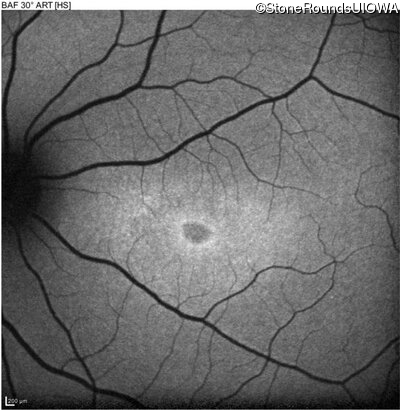

Age at visit: 17 years

OD OS

This 17 year old female first noted problems with her visual acuity around age 13 when she had trouble seeing the projector from the back of the classroom.

Age at visit: 16 years

Age at visit: 18 years

Age at visit: 22 years